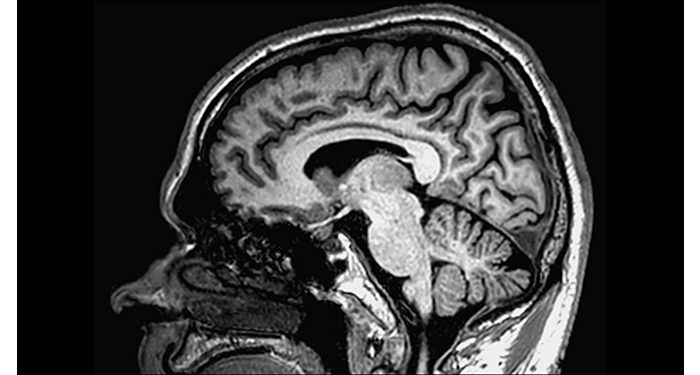

La IRM en un departamento de emergencias neurológicas para tomar decisiones rápidas y seguras

Cuando la IRM es la opción preferida, los pacientes con ED pueden obtener una IRM rápida y un diagnóstico rápido.

Protocolos cerebrales de UVM actualizados con los últimos métodos

UVM aprecia los últimos métodos neurológicos de resonancia magnética para el diagnóstico y el flujo de trabajo.